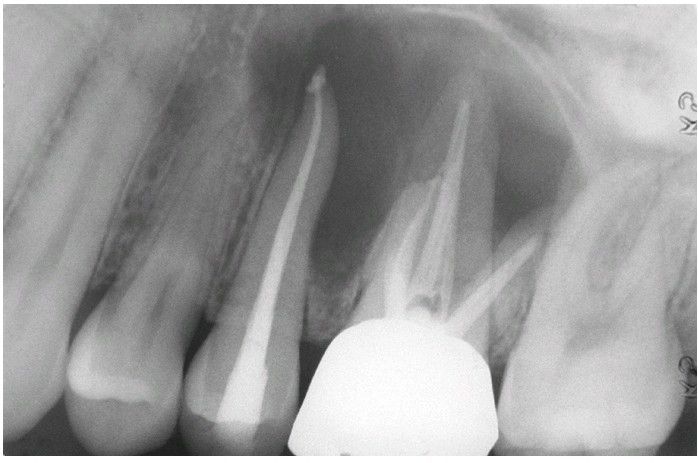

Granular Cell Odontogenic Tumor.

Radiolucent lesion involving the apical area of endodontically treated maxillary teeth.